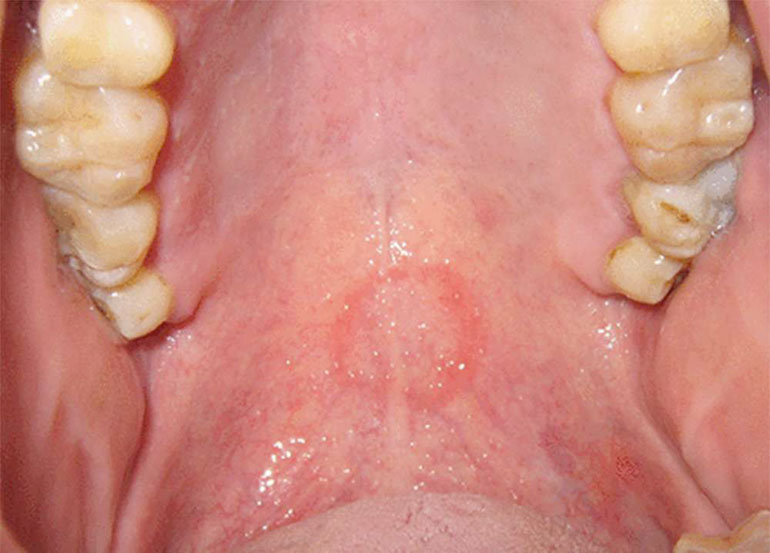

Un dentiste peut-il découvrir ou voir si vous avez fait une fellation dernièrement ? C’est que ce prétend ce dentiste brésilien. Apriori, les mouvements et les chocs provoquent une lésion très caractéristique (circulaire et profonde dans la gorge) au niveau du palais de la bouche. En plus, différentes bactéries peuvent être détectée dans la bouche. Mais rien d’inquiétant d’après lui, car tout reviendrait à la normale sous 48 heures. Fellation vue par un dentiste